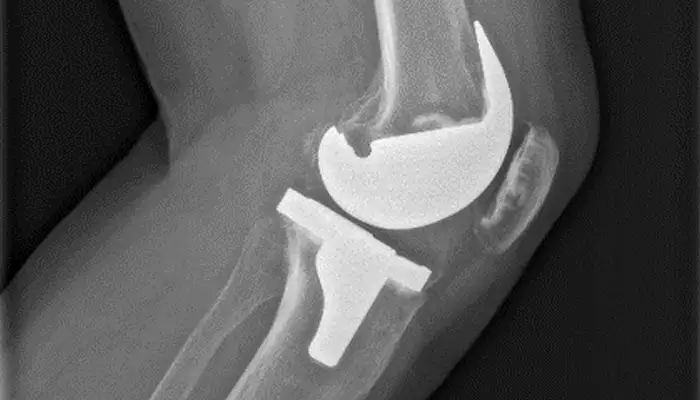

Prótesis total o parcial de rodilla (artroplastia). Consiste en la sustitución parcial o total de las superficies articulares desgastadas para restablecer la función de la rodilla.